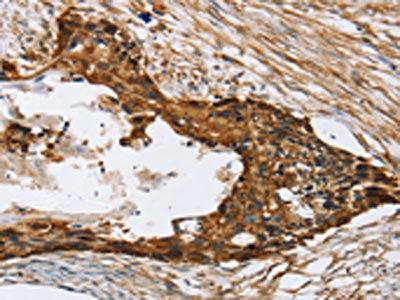

The image on the left is immunohistochemistry of paraffin-embedded Human breast cancer tissue using CSB-PA186945(TPD52L2 Antibody) at dilution 1/20, on the right is treated with synthetic peptide. (Original magnification: ×200)

The image on the left is immunohistochemistry of paraffin-embedded Human esophagus cancer tissue using CSB-PA186945(TPD52L2 Antibody) at dilution 1/20, on the right is treated with synthetic peptide. (Original magnification: ×200)